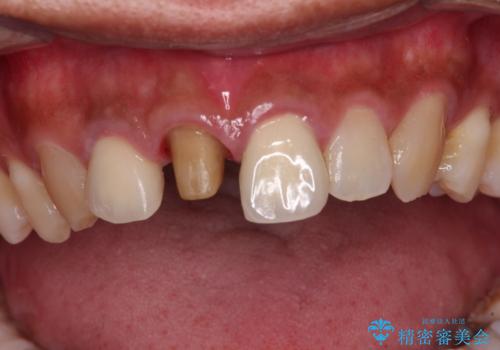

- 前歯の変色した歯を治したいことを主訴として来院された患者様です。

数年前、外傷により両隣の歯とともに根管治療を行い、その後両隣の歯はオールセラミッククラウンにて補綴したそうです。

時間の経過とともに、セラミックにしなかった当該歯の変色が目立つようになり、オールセラミッククラウンにて補綴することとしました。